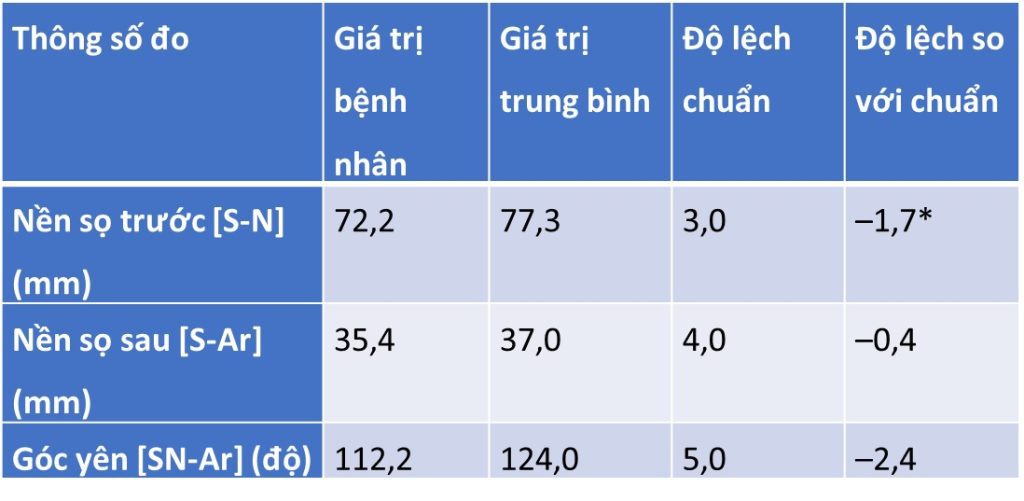

Tóm tắt phim sọ nghiêng (hình 2-16 và bảng 2-11 đến 2-14)

Tương quan xương hạng III với profile xương lõm, bao gồm:

- Xương hàm dưới nhô ra so với nền sọ

- Khớp cắn bù trừ với răng cửa hàm trên nghiêng ra trước và răng cửa hàm dưới nghiêng vào trong

- Chỉ số Wits loại III

- Profile mô mềm lõm

- Môi dưới nhô ra

- IMPA thấp hơn chuẩn 1,2 SD → răng cửa dưới hơi nghiêng vào trong.

- U1–Palatal plane cao hơn chuẩn 1,3 SD → răng cửa trên nghiêng ra trước.

- Góc liên răng cửa cao hơn chuẩn 1,1 SD → khớp cắn bù trừ (răng cửa trên nghiêng ra, răng cửa dưới nghiêng vào).

- Wits âm nhiều (–5,7 mm, lệch 4,7 SD) → đặc trưng của sai khớp cắn hạng III xương.